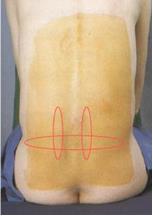

Quando è interessata la parte bassa lombare della colonna vertebrale, il dolore può sentirsi nella schiena bassa, la natiche e a volte dietro alle cosce.

- Il dolore si manifesta in corrispondenza della giunzione sacroiliaca ed aumenta alla digipressione.

- È irradiato all’inguine, ai glutei ed alla regione laterale della coscia.

- Il dolore aumenta in posizione seduta.